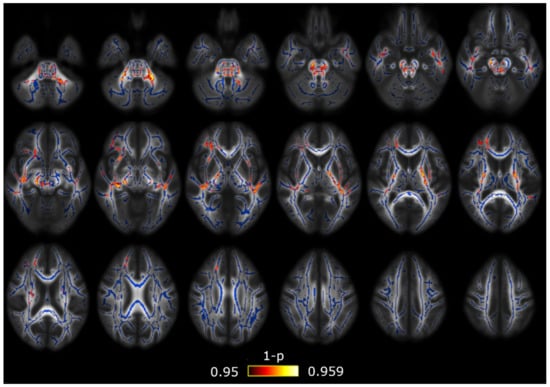

3.1. TBSS

3.2. TBSS with Covariates